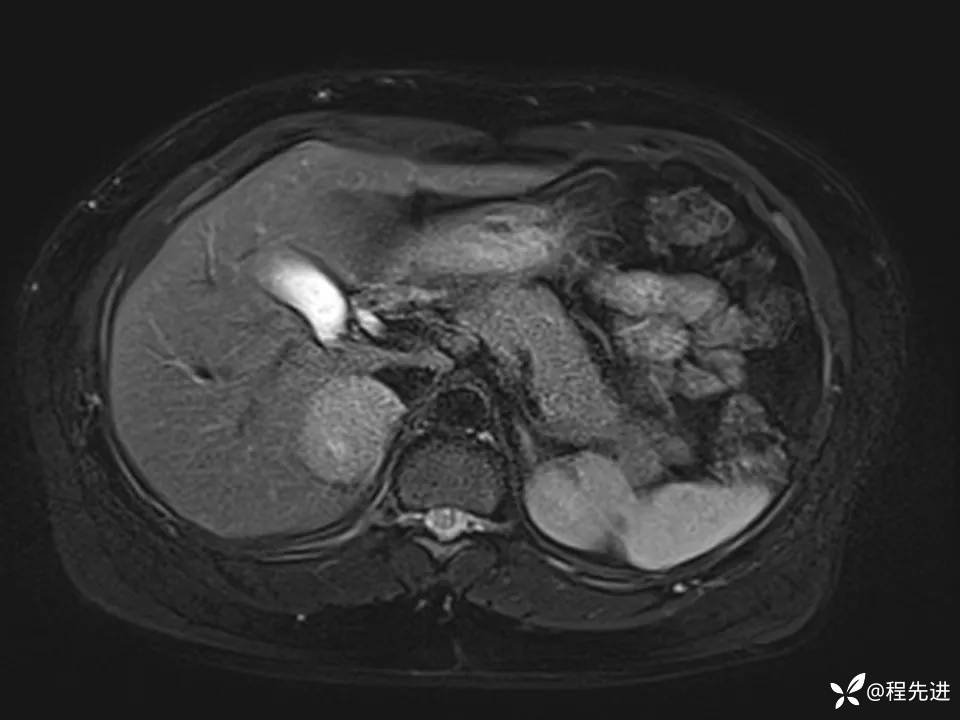

患者性别:女

患者年龄:44岁

简要病史:体检发现肝占位性病变2月余

既往:有高血压病史1月余,口服药物控制可

实验室检查阴性。